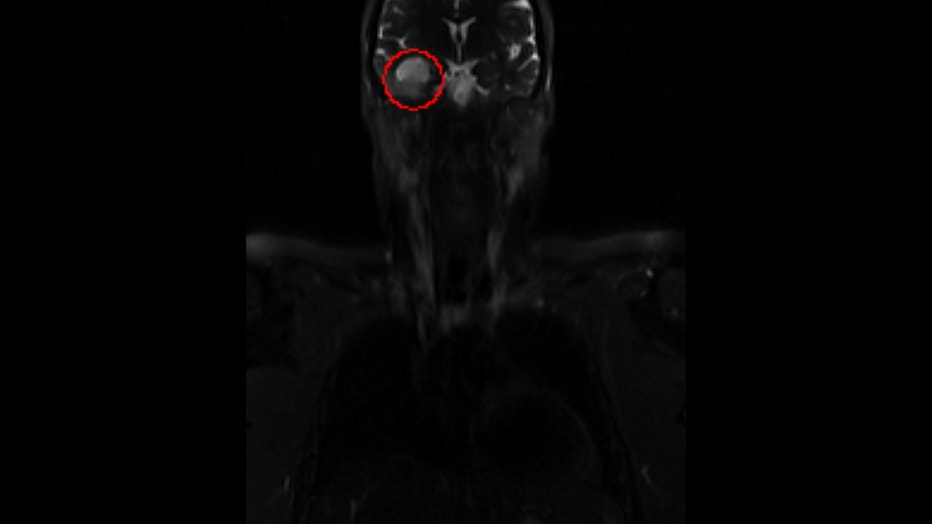

"When they give you a report, they start at the top of the body, and the first thing she said to me was, ‘You have a 2.3 by 2.4 centimeter mass in the right temporal lobe of your brain,’" Schaffer recalled. "That was not what I expected. I had no symptoms."

The scan detected a tumor the size of a walnut, a rare form of brain cancer. Surgeons at Phoenix's Barrow Neurological Institute were able to completely remove it just two months from her diagnosis. Andrea is grateful for the preventive MRI that ultimately saved her life.